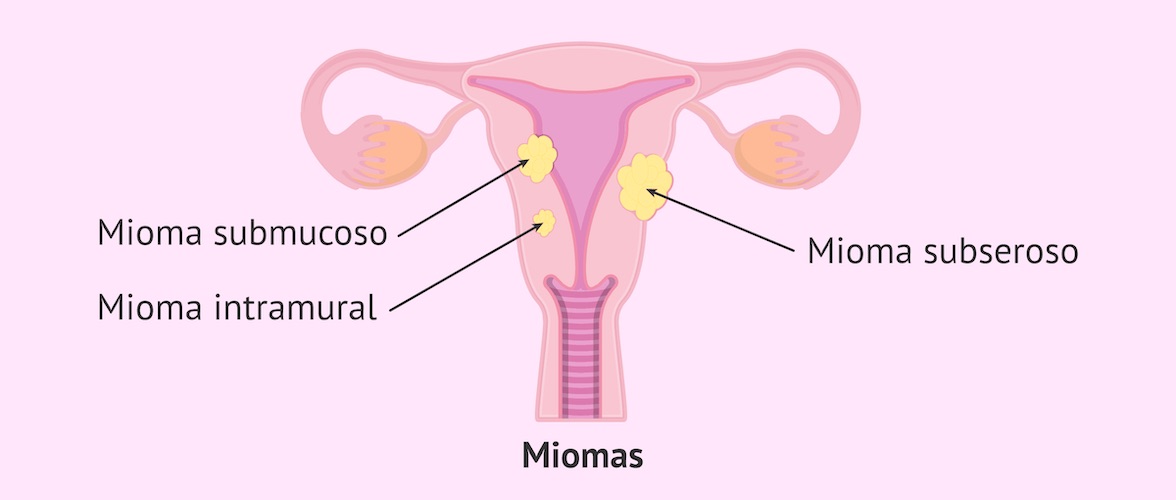

Sí. El tratamiento es quirúrgico y mínimamente invasivo:

- 🔬 Histeroscopía quirúrgica, para liberar las adherencias

- 🌸 Terapia hormonal posterior para favorecer la regeneración endometrial

👉 En casos bien tratados, es posible recuperar la anatomía uterina y mejorar el pronóstico reproductivo.